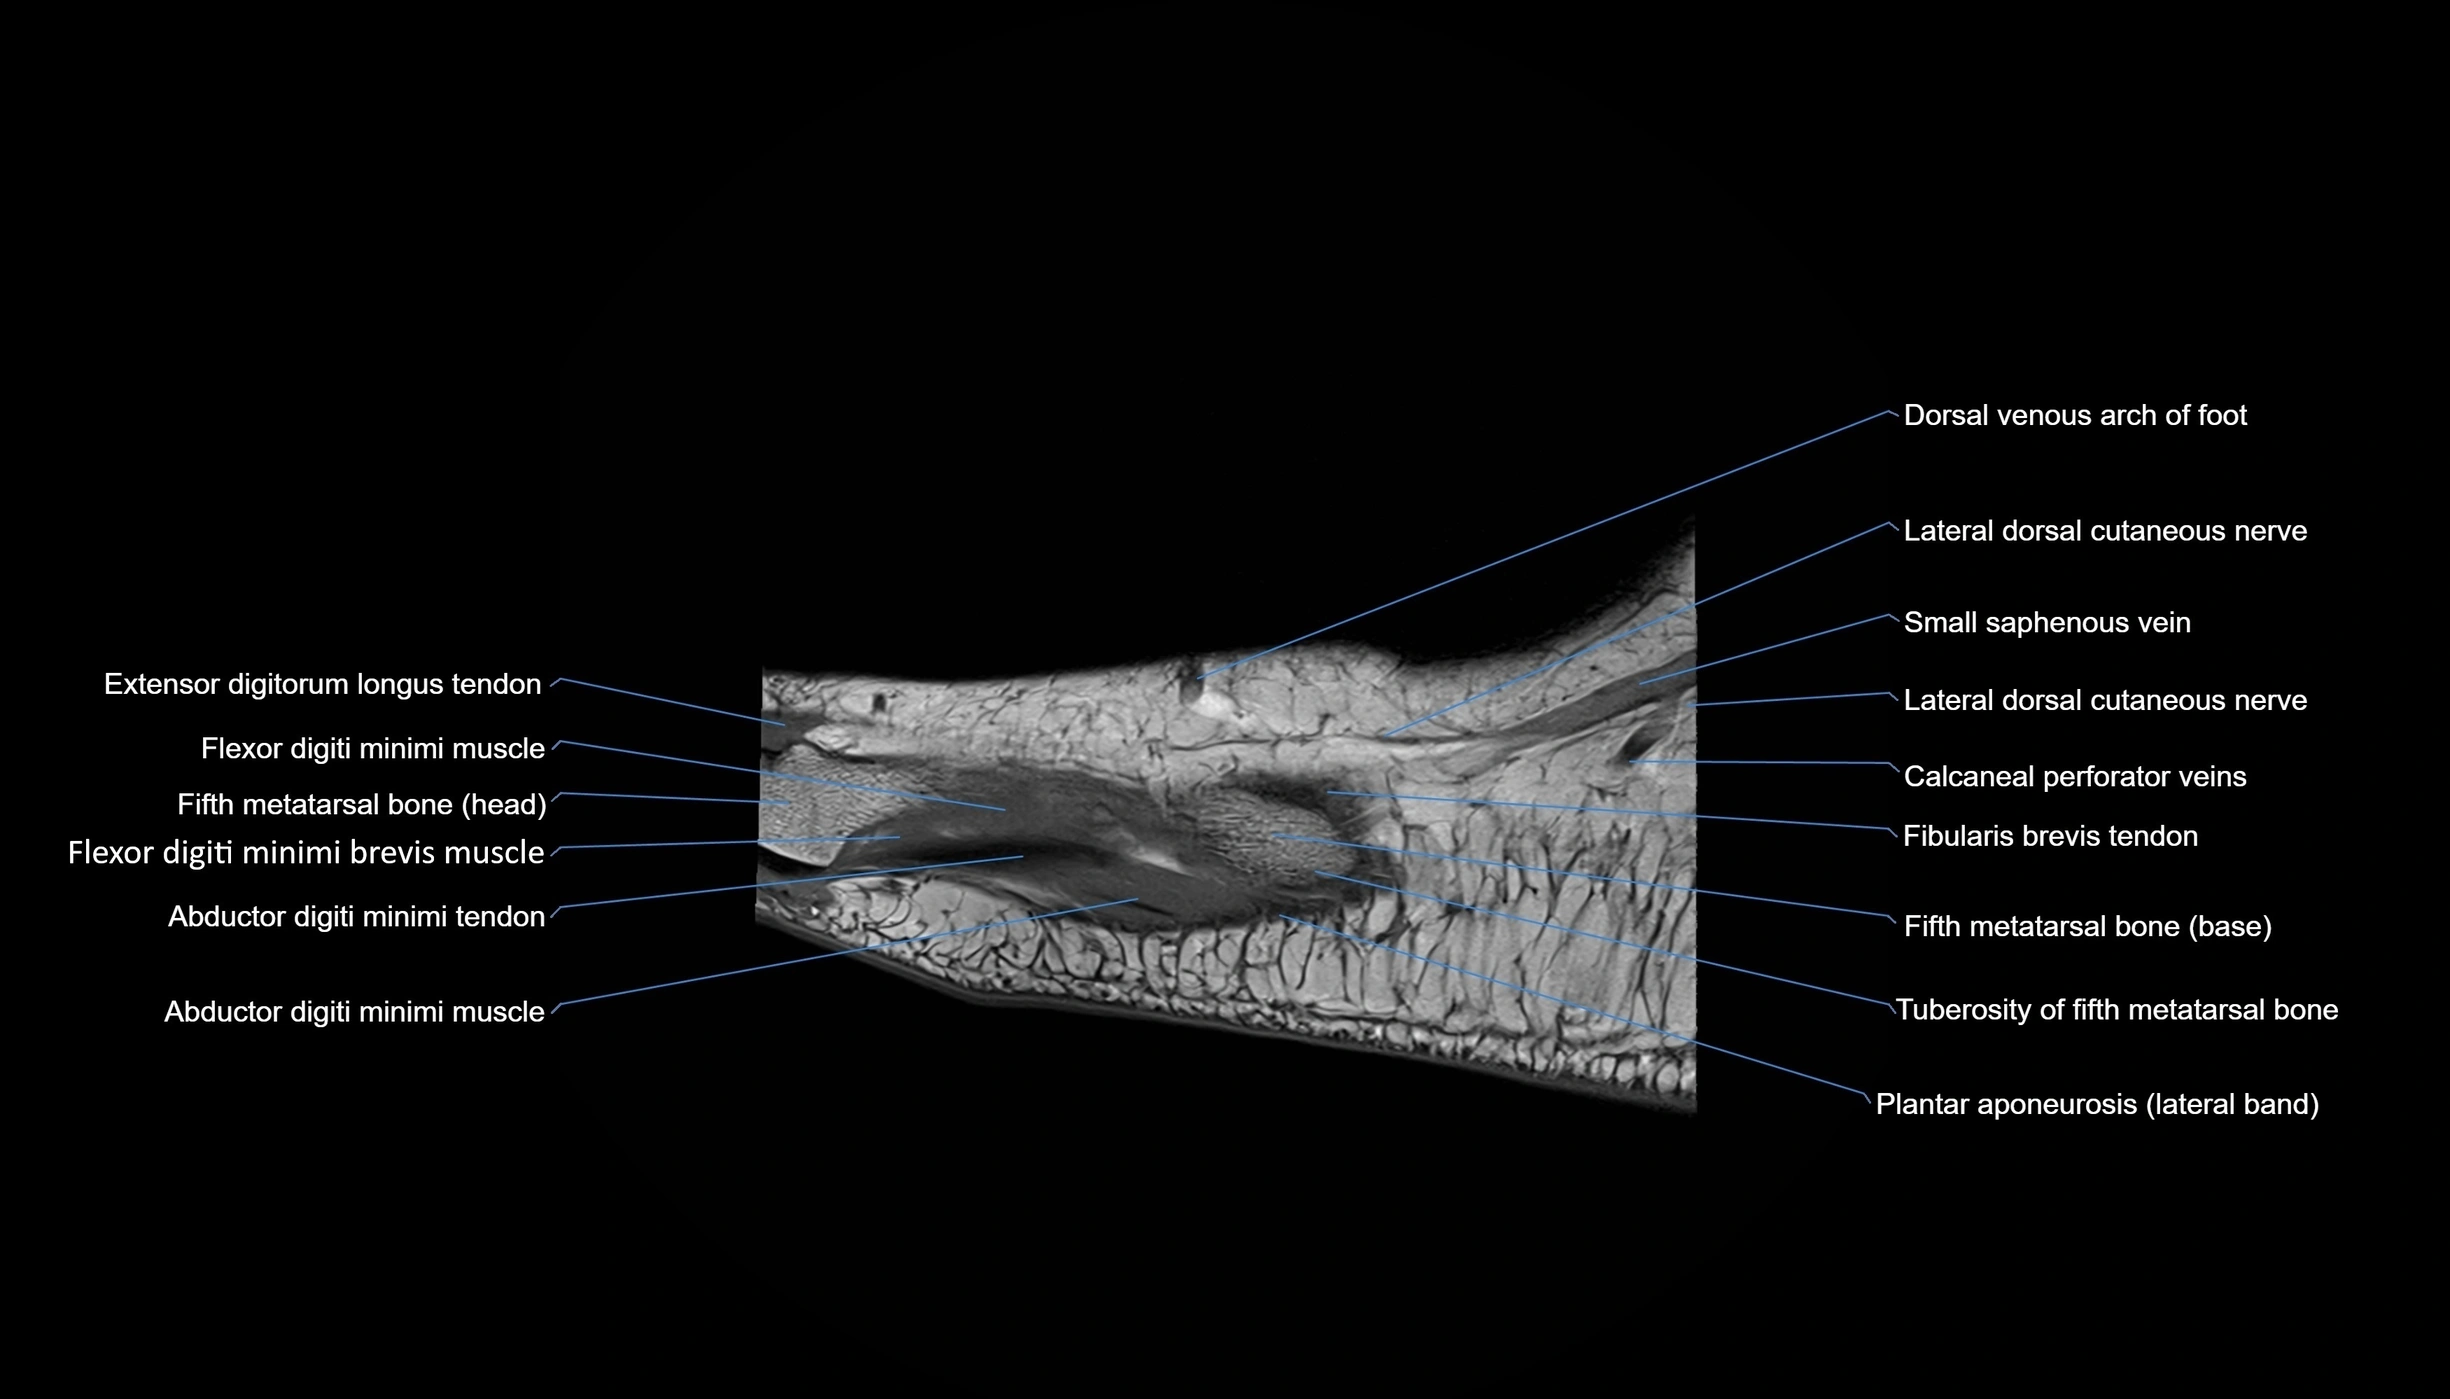

MRI image